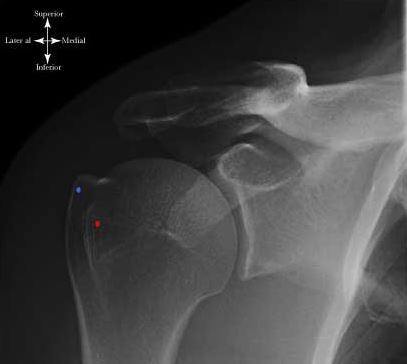

如何比较精准地来测量肩关节肱骨大结节骨折的移位程度么?

右肱骨大结节骨折 [病例帖]